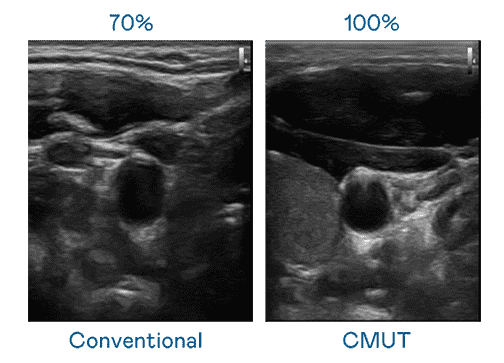

CMUT 技术是一种用电容式微机电元件来产生超音波讯号的技术。。与传统 PZT 压电式技术相比,,,,CMUT 频宽增加 30%,,更宽频的超音波讯号让影像解析度大幅提升,,是实现高影像品质医疗超音波扫描、、促进精准医疗发展的关键技术。。。。

大频宽带来超清晰影像

超音波影像的解析度高低,,,首先取决于探头能发出的讯号频宽。。william威廉中文官网 CMUT 可提供高清晰的超音波讯号,,,,提供高频宽、、高灵敏度、、、影像纹理细节更高的超音波影像,,,协助医护人员缩短影像判读时间及利用精准的医疗影像进行诊断。。。。